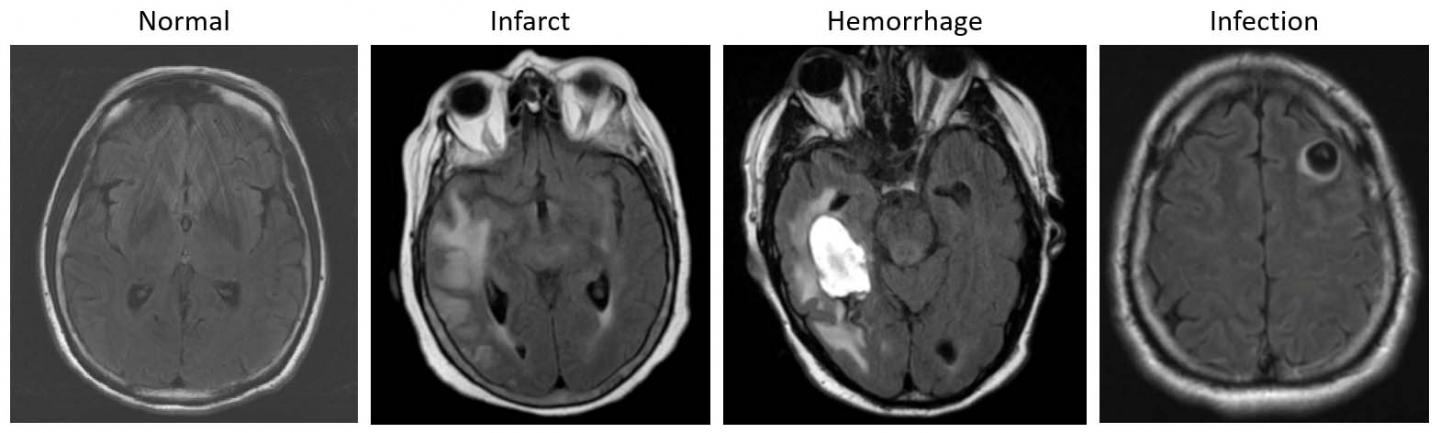

image: Examples of axial FLAIR sequences from studies within dataset A. From left to right: a patient with a 'likely normal' brain; a patient presenting an intraparenchymal hemorrhage within the right temporal lobe; a patient presenting an acute infarct of the inferior division of the right middle cerebral artery; and a patient with known neurocysticercosis presenting a rounded cystic lesion in the left middle frontal gyrus.